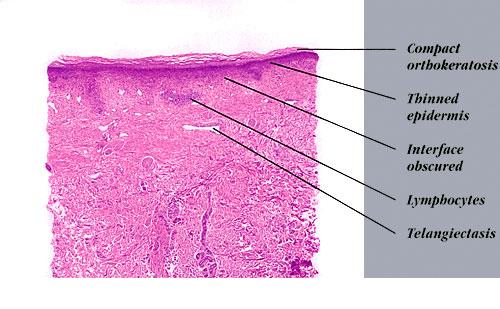

Arsenical keratoses = التقران الزرنيخي ARSENICAL KERATOSES Arsenical keratoses (ArKs) are precancerous lesions found in association with chronic arsenicism. These lesions have the potential to develop into invasive SCC. Arsenic is a ubiquitous element that has no color, taste, or odor. It has the potential to cause characteristic acute and chronic syndromes in persons exposed […]